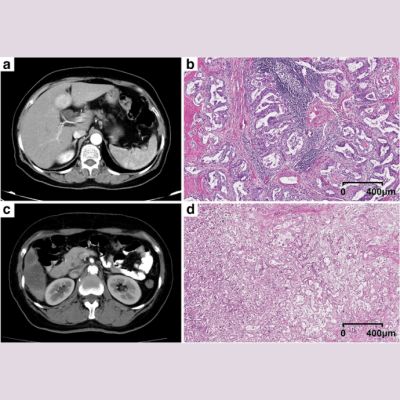

Using a powerful 9.4-Tesla MRI — the first of its kind for human imaging — researchers at the University of Illinois at Chicago have obtained the most detailed MRI images of the brain so far to show that while the brain shrinks with age, brain cell density remains constant. The findings are reported in the journal NMR in Biomedicine.

The 9.4-Tesla images provide the first evidence that in normal ageing, cell density is preserved throughout the brain, not just in specific regions, as previous studies on human brain tissue have shown. The new findings also suggest that the maintenance of brain cell density may protect against cognitive impairment as the brain gradually shrinks in normal ageing.

"The information provided by these 9.4-Tesla scans may be very useful in helping us to detect tiny losses of brain cells and the reduction in cell density that characterises the early stages of neurodegenerative diseases that can take decades to develop before symptoms appear, like Alzheimer's disease," says lead author Dr. Keith Thulborn, director of MRI research in the UIC College of Medicine.

"If we can identify when Alzheimer's pathology starts, the efficacy of new drugs or other interventions to slow or prevent Alzheimer's disease can be tested and monitored when the disease starts, instead of after it's developed for 20 or 30 years and becomes clinically apparent," explains Dr. Thulborn, who is professor of radiology, physiology and biophysics.

For this study, Dr. Thulborn and his team scanned the brains of 49 cognitively normal adults ranging in age from 21 to 80. All had at least a college education and were employed or, if retired, were active in their communities. All subjects were without major medical, neurological or psychiatric disease and scored within the normal range for mental status.

The 9.4 Tesla MRI measures sodium ions, which are present throughout the body and are pumped in and out of neurons to generate the electric potentials needed to spark nerve impulses. Sodium concentrations in the brain reflect neuron density. Areas of low sodium concentration indicate lots of neurons packed tightly together, while higher sodium concentration can indicate more space between cells — or the loss of cells, as in the case of neurodegenerative diseases.

The 9.4 T magnetic field is more than three times stronger than that of a conventional MRI machine and is currently approved only for research. The strongest MRI units approved for clinical use are 3 T.

Dr. Thulborn thinks the ultra-high-field scanners eventually will be approved for clinical use. As he points out: "We can use the 9.4 T to look at brain cell loss in real time in patients experiencing stroke, or to see whether chemotherapy for brain tumours is working in higher resolution that is just not available using the current 3 T clinical scanners."